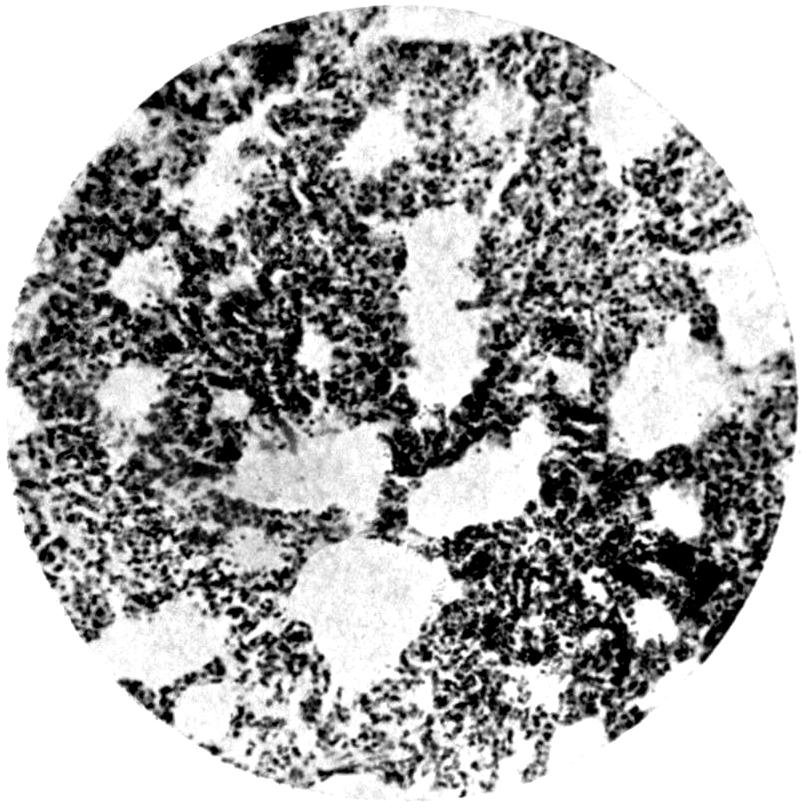

Plate II. 93